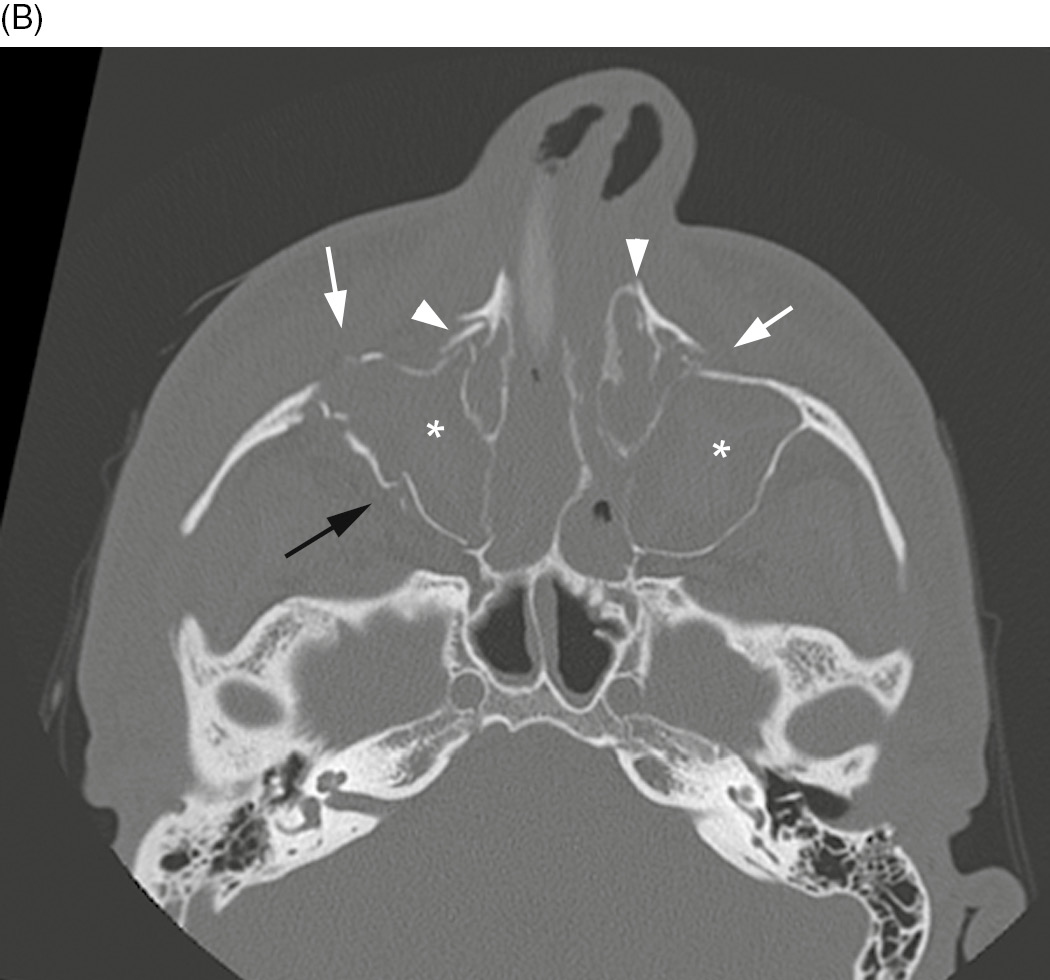

Complex facial fractures

Complex facial fractures 142 photos